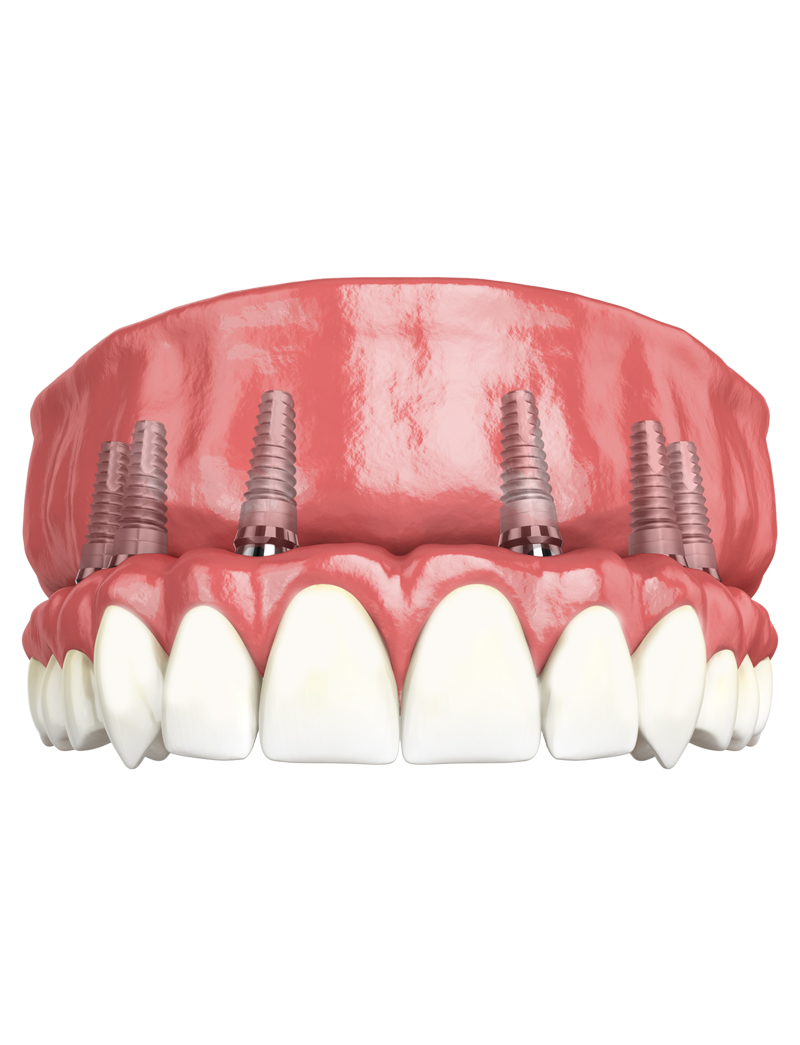

The newAll on Six implant (All on 6) technique could be right for you if you already have a denture or a skeleton and you need to extract the last remaining teeth

• This solution is ideal if you want to have fixed teeth quickly, easily and without painful bone grafting;

• This technique can also be applied for those who are edentulous (toothless) for a long time;

Another great advantage that derives from the All on 6 method is the immediate load, on the inserted implants your new fixed teeth are fixed in the same session or at most in a second sitting after a few days.

Thanks to immediate loading, if there are certain conditions, it is no longer necessary to wait months before chewing on new teeth!